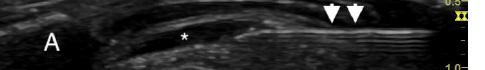

Laboratory results showed white blood cell count (WBC) of 11.59 x 109 cells per liter (x 109/L) (reference range: 4.50 – 11.0 x 109/L). Erythrocyte sedimentation rate and C-reactive protein were not sent. Computed tomography (CT) of the neck with intravenous (IV) contrast was done, as the differential diagnosis included mastoiditis, retropharyngeal abscess, and other deep space neck infection. Computed tomography results showed prominent amorphous calcification inferior to the anterior arch of the first cervical vertebrae, highly suggestive of calcific tendonitis of the longus colli muscle (Image 1), with diffuse retropharyngeal edema (Image 2).

showing focal calcification (arrow) in the longus colli tendon at the level of the first and second cervical vertebrae. Image 2. Sagittal computed tomography image in soft tissue window showing diffuse retropharyngeal edema (arrows).